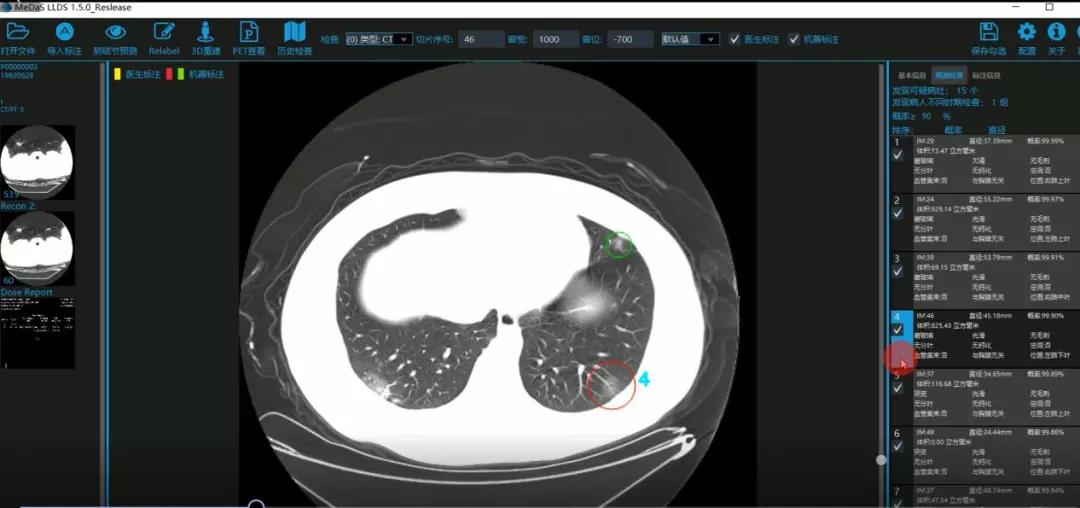

医护人员的好帮手:基于深度学习的新冠肺炎早期检测筛查系统

西电beat365官方网站智能软件与系统新技术研究所副教授张亮的爱人是西安交通大学第二附属医院抗疫一线的影像科医生,疫情发生以来,他们讨论最多的就是新型冠状病毒感染者的早期诊断问题。作为一名医护家属,身为高校科研工作者,张亮深知快速准确地诊断新冠肺炎早期患者对控制和防治疫情的重要性和挑战性。他与团队成员主动出击,通过远程网络会议,在前期医学影像处理的研究基础上加速科研攻关,反复讨论方案,屡次设计模型,与上海宽带技术及应用工程研究中心、上海交通大学医学院附属瑞金医院等合作单位的人员多次标注整理患者肺部CT影像数据到深夜。与此同时,他们依托上海瑞金医院、西安交通大学第二附属医院等的新冠肺炎疑似、确诊患者肺部CT影像,通过综合分析新冠肺炎患者的肺部CT影像特点(磨玻璃、体积大小、位置等特征),张亮团队加快技术攻关,设计开发了基于深度学习的新型冠状病毒的早期检测筛查模型系统。

对应新冠肺炎CT病灶检测效果

令人欣喜的是,通过对实际门诊数据排查测试,该模型可以减轻医护人员近80%的工作量,新冠肺炎患者的检测召回率超过95%。目前,模型系统正在进行最后的调试工作,很快投入到“战疫”一线,缓解医护人员紧缺、确诊检测工作耗时较长等问题,减少医护人员的工作时间和劳动强度,提高工作效率。